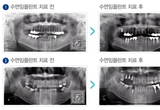

‘치과공포증’을 이겨내는 치료법은?

이젠 당당하게 치과가 갈 수 있다!